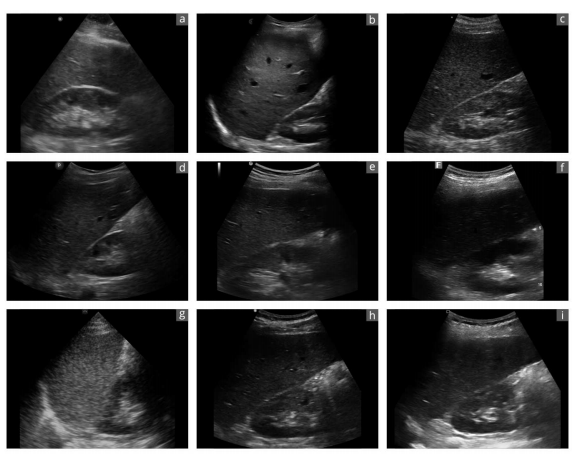

Figure 4. Exemplary sonographic images of a liver-kidney section from the same subject using different devices